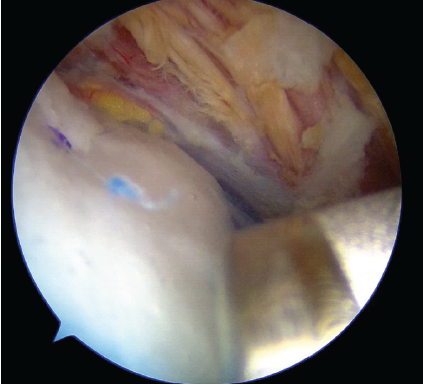

A 60-year-old man presented to our clinic with the right shoulder pain. On examination, his range of motion was 150° in forward flexion and 60° in external rotation, without mechanical catching. Magnetic resonance imaging (MRI) revealed a partial-thickness tear of the supraspinatus tendon (Fig. 1), and conservative management was initiated. However, as his nocturnal pain worsened, arthroscopy was performed 3 months later, confirming a partial tear. Arthroscopic rotator cuff repair was then carried out with augmentation using a medium-sized REGENETEN® implant, which was secured on the tendon surface (Fig. 2).

Figure 2: Arthroscopic view after rotator cuff repair with REGENETEN®. Intraoperative arthroscopic image of the right supraspinatus tendon after rotator cuff repair augmented with a medium-sized REGENETEN® bioinductive collagen implant.